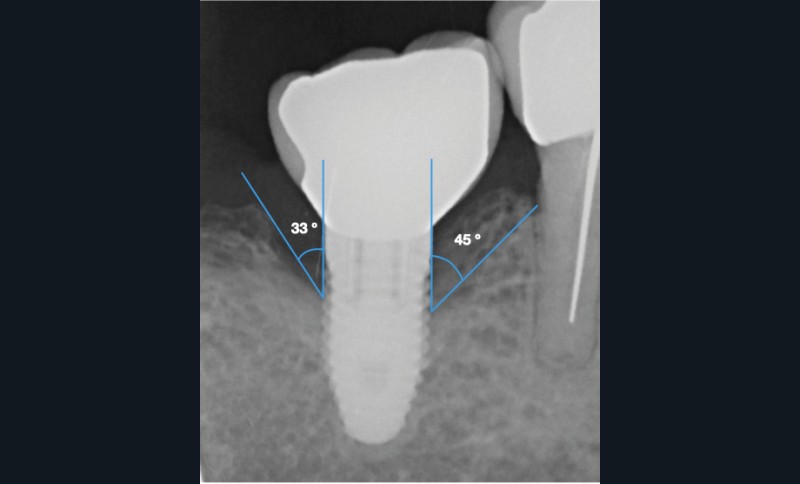

- Péri-implantite sur l’implant 47, diagnostiquée en août 2022

- Implant posé en 2017

- Nobel Replace Select RP (4,1 x 10 mm)